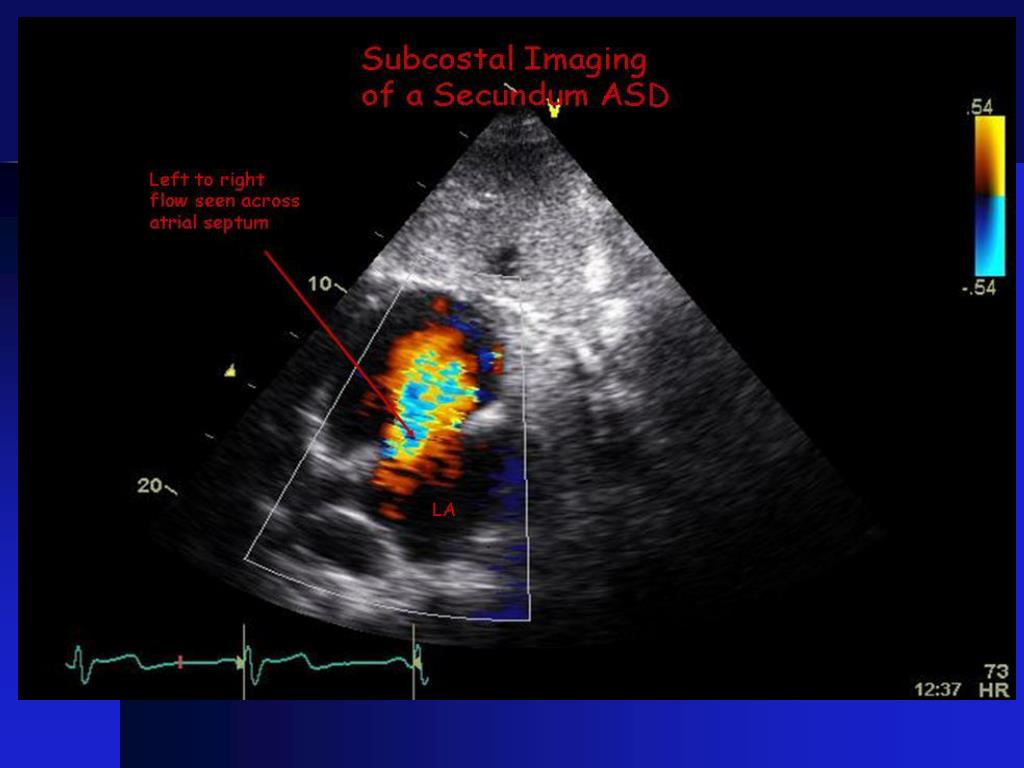

The amount of pulmonary blood flow to systemic blood flow in absolute terms. The hole increases the amount of blood that flows through the lungs. An atrial septal defect (asd) is a direct communication between the cavities of the atrial chambers that permits shunting of blood.

Although the defect often causes no symptoms until. It is located in the. To calculate the qp:qs in patients with asd’s, follow these steps: